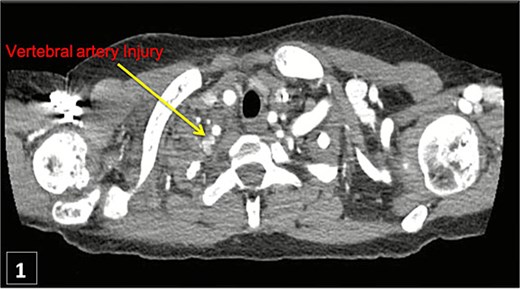

An urgent CTA revealed contrast extravasation from the proximal left vertebral artery, ~1 cm from its origin at the subclavian artery (Fig. 1). He was immediately taken to the angiography suite. Via left brachial access, a balloon-expandable covered stent (4 × 29 mm) was deployed, completely sealing the injury and restoring flow (Fig. 2). Post-procedure imaging confirmed no further extravasation (Fig. 3). The patient stabilized, vasopressors were weaned, and he was discharged without neurologic deficits. The patient’s clinical course and management are summarized in a timeline (Fig. 4).

Thoracic CT angiogram shows contrast extravasation from left vertebral artery after CVC.